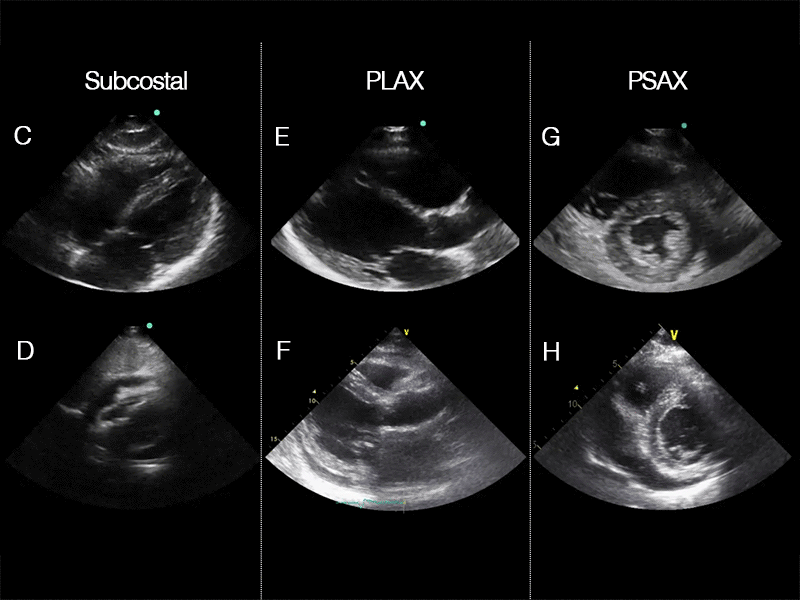

SC, PLAX and PSAX views

Comparison of normal and pericardial effusion in three cardiac views: This clip consists of six views, comparing normal cardiac views (top row) with pericardial effusion (bottom row). The left column shows the subcostal (SC) view, the middle column shows the parasternal long-axis (PLAX) view, and the right column shows the parasternal short-axis (PSAX) view. In the lower row, the anechoic (black) border around the heart represents pericardial fluid, highlighting the difference between the normal and pathological findings.